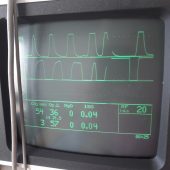

- Narkoseüberwachung ist einfach unerlässlich.